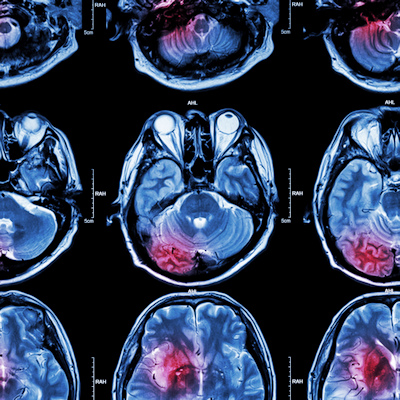

Researchers used diffusion tensor imaging, an MRI technique, to study the impact of football heading on the brain. This method tracks the microscopic movement of water molecules through brain tissue to characterize the brain's microstructure. Image and caption courtesy of the RSNA.

The researchers wanted to study the association of football heading over two years with change in brain microstructure and cognitive performance in adult amateur players. They used DTI, an MRI technique that characterizes the microstructure of the brain by tracking the microscopic movement of water molecules through brain tissue.